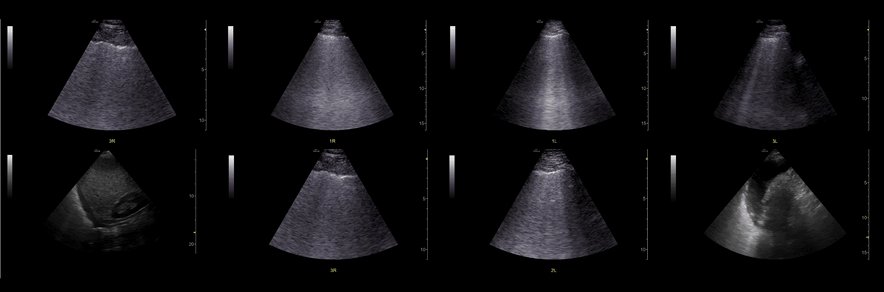

We see B lines diffusely, with mostly regular pleura other than some hint of pleural irregularity in 3R but not much. And small bilateral pleural effusion. How does this influence post-test probability for cardiogenic pulmonary edema

10/

How does this influence post-test probability for PNA?

11/